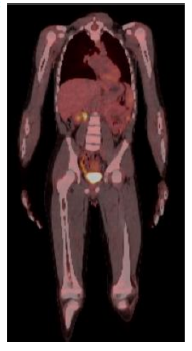

图3:第三次HER2 CAR T细胞输注6周后,正电子发射断层扫描(PET-CT)的代表性图像显示骨髓或其他部位无FDG高代谢灶